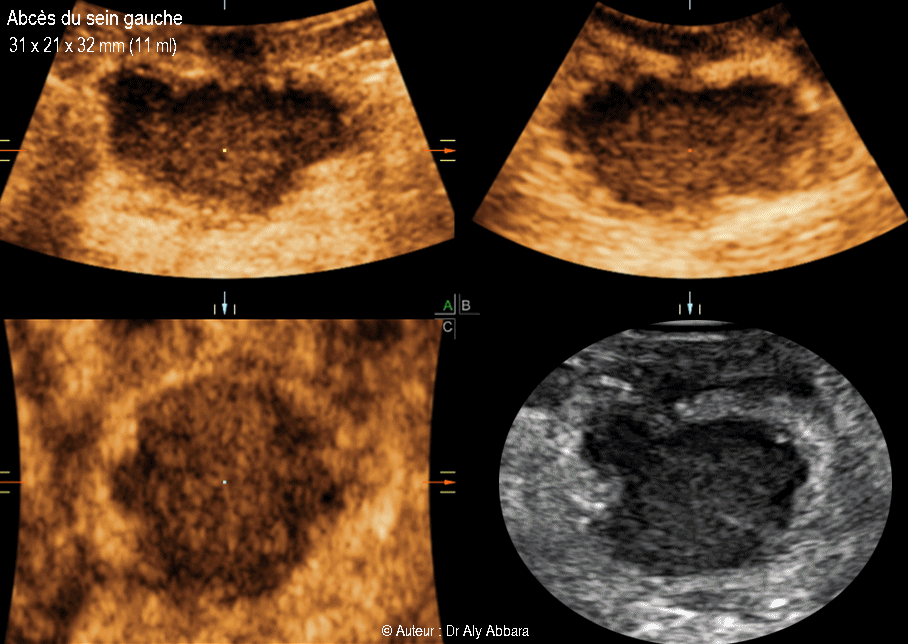

Abcès du sein gauche - خُراج الثدي الأيسر

Image animée montrant l'aspect échographique d'un abcès du sein

de (31 x21 x 32 mm de diamètre, soit 11 ml de volume) chez une femme

âgée de 30 ans allaitant son nourrisson depuis deux mois.

Ces images échographiques montre que cet abcès est composé :

• D'une néo-cavité formée par l'infection aiguë et limitée par une coque hyperéchogène d'épaisseur irrégulière et festonnée ; elle est constituée de tissu conjonctif fibreux inflammatoire réactionnel.

La formation de la coque autour de l'abcès permet de circoncire l'infection et de bien limiter son extension et diffusion vers les tissus avoisinant.

• Le contenu de l'abcès parait hypoéchogène, il s'agit du pus :

• Chez cette femme qui allaite, le pus est mélangé également au lait maternel.